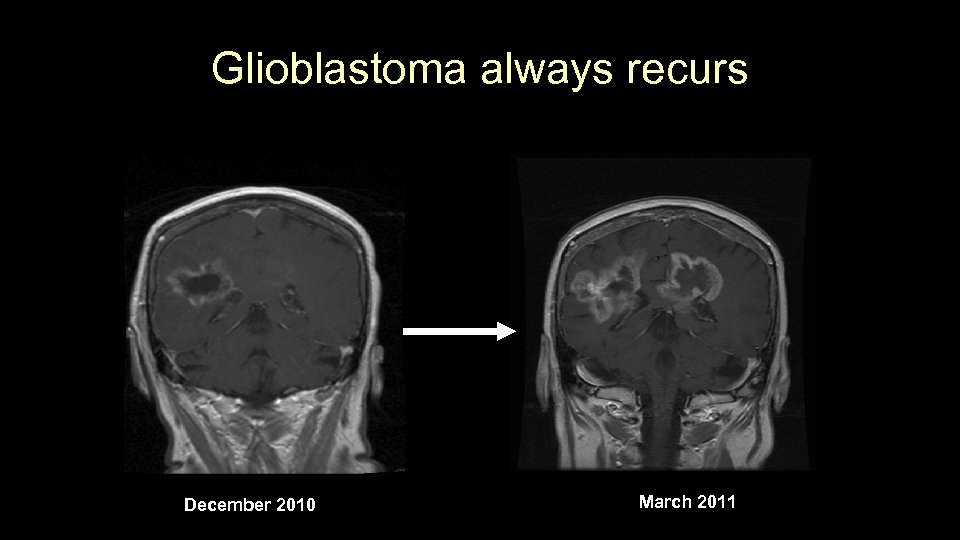

Glioblastoma always recurs December 2010 March 2011